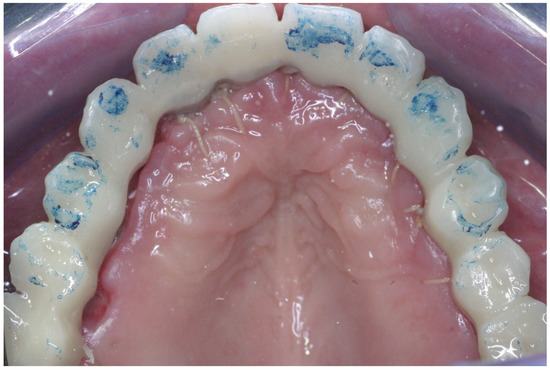

2.3. Prosthetic Protocol

- Plaque index (PI)—Using a disclosing solution, the plaque was measured at four sites per implant, and the percentage of visible plaque was calculated [22].